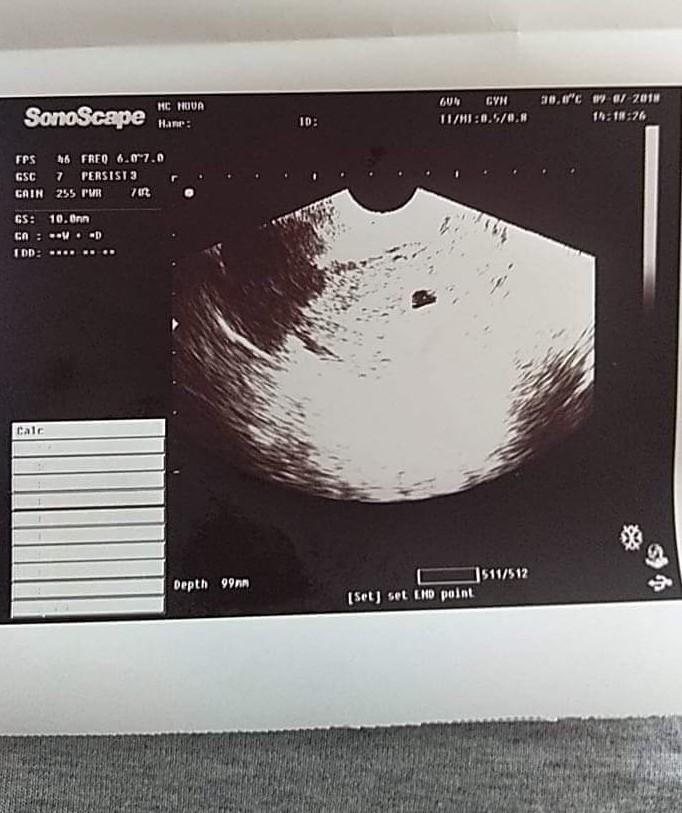

Обичайните симптоми на бременността включват болезнени и подути гърди, умора, придърпване и болки в корема, често чувство на сънливост, повишен апетит, подут корем и чести посещения на тоалетната. Важно е да се отбележи, че симптомите на бременността могат да варират значително от жена до жена. Обичайните симптоми на бременност включват умора, ранно заспиване, отвращение към кафе, повишено вагинално течение, болезнени гърди, промени в настроението, повишен апетит , обилно воднисто течение и бяло вагинално течение. Тези симптоми обикновено са безвредни и не трябва да предизвикват безпокойство. Симптомите на ранна бременност включват гадене, подут корем, усещания за упъване и боцканe в корема, обилно кафяво зацапване или кървене, чувствителни гърди и повишен апетит.